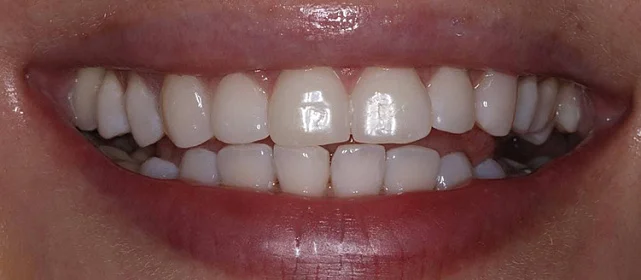

Результат

Зубы выровнены, скученность устранена. Установлены несъёмные ретейнеры на обе челюсти, сняты сканы для ретенционных кап. Ортопедия не требуется, рекомендовано лечение у терапевта.

Решение: Установили брекеты на обе челюсти. Расширили дуги, убрали скученность — всё за 15 месяцев. Визиты раз в 4–6 недель для замены дуг. После снятия зафиксировали ретейнеры на обе челюсти, сняли сканы для кап. Ортопед подтвердил, что протезирование не требуется. Терапевт рекомендовал лечение — пациентка записана.

Пятнадцать месяцев!! Я морально готовилась к двум годам минимум, начиталась всякого в интернете. Виктория Юрьевна на первой консультации сказала, что случай не самый сложный и должны уложиться побыстрее. Так и вышло. Из неприятного — первая неделя после установки и пара дней после каждой замены дуги. В остальном нормально, привыкла быстро. Когда сняли и я увидела зубы — не поверила, что это мои. Теперь вот к терапевту надо сходить, подлечить пару зубов, и вообще всё.